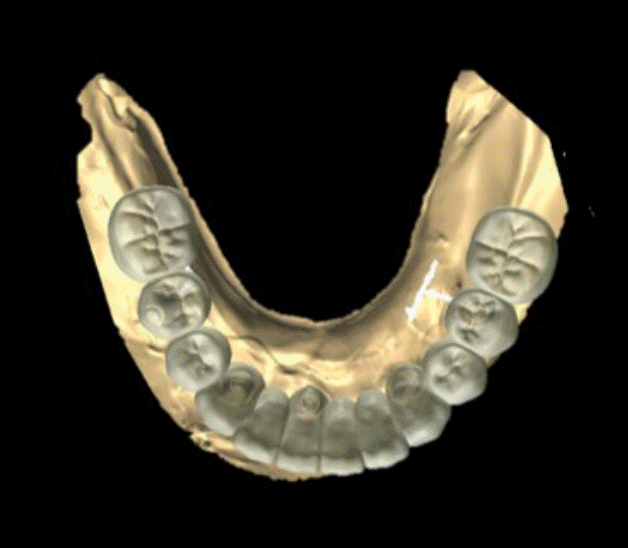

본 증례는 44세 여환으로, 하악 의치가 계속 탈락하여 재제작을 원한다는 주소로 내원하였다. 상악은 고정성 수복물, 그리고 하악은 총의치를 착용 중이었고 하악 양측 구치부의 심한 골 흡수로 인해 유지력 소실로 불편감을 호소하였다. 3개월 전 하악 양측 견치를 발거한 이후로 하악 국소의치를 총의치로 전환하였고, 총의치는 구치부의 심한 교합면 마모와 의치의 후방부가 후구치 삼각 융기를 피개하지 않는 형태였다. 전신 병력으로는 지적장애 및 골관절염으로 약 2개월 간 약물 복용 중이었다. 상악 우측 제1대구치와 제2대구치, 제1소구치 그리고 제2소구치는 우식이 진행된 상태였고, 우측 제2소구치와 우측 제1대구치는 근관치료가 완료된 후 수복되지 않은 상태였다. 상악 좌측 제1소구치와 제2소구치, 그리고 제1대구치 수복물 하방으로 이차 우식이 진행된 상태였고, 전체적으로 교합평면이 균일하지 않은 형태였다(Figs. 1-3).상악 우측 구치부의 수복되지 않은 치아와 상악 좌측 보철물 하방의 이차 우식이 있는 치아는 모두 우식 제거가 필요하여 양측 구치부 각각 3개의 치아는 재수복을 결정하였고, 하악은 구치부의 심한 치조골 흡수로 인해 의치 사용은 불가할 것으로 판단하여 전방부에 임플란트를 식립하여 구치부는 캔틸레버 형태를 가지는 all-on-X 수복을 계획하였다. 의치의 수직고경에 맞춰 교합 평면을 균일하도록 하여 왁스업 시행하였고(Fig. 4), 이후 적절한 교합 수직 고경의 임시 의치를 제작하였다. 약 2개월의 적응기간을 거쳐 의치 적응도와 수직 교합 고경을 평가하였고 적절한 기능과 심미를 확인하였다. 상악 우측 제1소구치와 제2소구치, 제1대구치 그리고 상악 좌측 제1소구치와 제2소구치, 제1대구치는 우식을 제거한 다음, 임시 보철물로 재수복하여 적절한 교합 평면을 설정하였다(Fig. 5).환자가 적응한 임시 의치를 모델 스캔(Medit T710, Medit, Seoul, Korea)하여 프린팅용 레진(Graphy Tera Harz SG-100, Graphy, Seoul, Korea)을 이용하여 3D 프린팅하였고, 출력된 의치에 방사선 불투과성 레진(G-æenial Universal Flo, GC, Luzern, Swiss)을 부착하여 레진 마커를 형성하였다. 레진 마커를 부착한 프린팅 의치를 장착한 채로 콘빔 전산화 단층촬영(CBCT, R2 Studio Q, Megagen, Seoul, Korea)를 촬영하였다(Fig. 6). 촬영한 CBCT 데이터와 의치 스캔 파일을 중첩하여 CAD 소프트웨어(R2 Studio Q, Megagen, Seoul)를 통해 이상적인 임플란트 식립을 계획하였다. 전후방 거리를 연장하여 적절한 캔틸레버를 부여하기 위해 전방부에 3개의 임플란트를 식립하고, 양측 후방부에는 약 30도 경사진 임플란트를 식립하도록 계획하였다(Fig. 7).가이드는 상악의 자연 치열과 대합되는 의치 복제 형태의 상부 가이드, 그리고 가이드 핀이 존재하는 하부 가이드로 이루어지도록 디자인되었다(Fig. 8). 상부 가이드는 임시 의치의 스캔 데이터를 이용해 상부 가이드의 하부면과 하부 가이드의 상부면이 장착되어 구내에서 적합될 수 있도록 CAD 소프트웨어(Meshmixer, Autodesk, San Francisco, CA, USA) 상에서 디자인되었다. 임시 의치의 하부면과 하부가이드의 하부면을 치은과 중첩시켜 어버트먼트의 위치에 홀을 형성한 다음 3D 프린팅(Graphy Tera Harz SG-100, Graphy, Seoul, Korea) 하였다. 수술 당일 장착될 임시 보철물 또한 동일한 CAD 소프트웨어를 통해 제작하였다.수술 당일 이중 가이드를 구내에 장착하여 하부가이드를 고정 핀으로 고정시킨 후(Fig. 9), 계획된 위치에 임플란트 고정체를 식립하였다. 임플란트는 5개 모두 외부 연결형 고정체(AnyOne External, Megagen, Seoul, Korea)를 사용하였고, 식립 시 식립 토크는 모두 40N 이상, ISQ는 70이상으로 양호한 초기 고정력을 확보하였다(Fig. 10). 즉시 부하를 위해 기성 어버트먼트를 체결하였고, 임시 보철물을 장착하여 양측 소구치부에서의 균일한 교합을 확인하였다(Fig. 11).임플란트 주위 골과 치은의 회복을 위해 약 2달간 임시 보철물을 경과 관찰하였고, 이후 최종 보철을 위한 인상 채득을 시행하였다. 상하악 임시 보철물을 장착한 중심교합 상태에서 구내 스캔(Trios 4, 3 Shape, Copenhagen, Denmark)을 시행하여 악간 관계를 채득하였다(Fig. 12). 임시 보철물을 제거한 상태에서 하악의 전방부 3개의 임플란트에 scan body(Scan Abutment, Megagen, Seoul, Korea)를 연결하고, 양측 최후방 임플란트 2개에는 각각 Ti base multi-unit abutment(multi-angled abutment, Osstem, Seoul, South of Korea)를 30Ncm으로 체결한 후 multi scan body(TS Multi scanbody, Osstem, Seoul, Korea)를 연결하여 구내 스캔(Trios 4, 3Shape, Copenhagen, Denmark)을 시행하였다. 이후 스캔 바디를 연결하여 채득한 스캔 파일을 상하악 임시 보철물 상태에서 채득한 스캔 파일과 중첩하여 CAD 소프트웨어(exocad GmbH, Darmstadt, Germany)에서 최종 보철물을 디자인하였다(Fig. 13).최종 보철물은 양측 최후방 임플란트 고정체에 각각 Ti-base(TS multi Ti base, Osstem, Seoul, Korea)와 접착된 나사 유지형 단일 지르코니아 크라운으로, 지르코니아 블록(Zircen, Kuwotech, Gwangju, Korea)을 밀링하여 제작하였고, 치경부 하방으로 포세린으로 치은 형태를 부여하였다. 전방부 3개의 임플란트 고정체에는 맞춤형 지대주를 제작하여 30N으로 체결하였고, 양측 최후방 고정체는 20Ncm으로 체결한 후 레진 시멘트(Rely X U200; 3M ESPE, St. Paul, MN, USA)로 접착 시행하였다. 장착 후 중심교합시 양측의 제1대구치 부위에서 교합력이 적게 가해지도록 교합 조정 시행하였으며, 전방과 측방운동시에 임플란트 상호보호교합이 되도록 조정하였다. 또한 연결부 하방으로 치실을 통과시켜 치은 점막 사이 공간을 평가하였으며, 구강 위생 관리의 용이성을 확인하였다. 이후 1주, 1개월, 3개월 경과 관찰하였고, 환자는 저작이나 심미, 발음 등에서 만족해하였다(Figs. 14 and 15).

Fig. 14.

The final prosthesis is functionally and esthetically fitted with the patient. A. Right side view. B. Frontal view. C. Left side view.